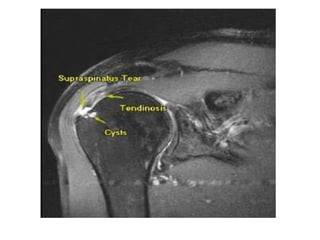

MRI

• A patient with symptoms of

subacromial impingement may show

increased signal in the supraspinatus

tendon on T2-weighted MRI consistent

with tendinopathy;

• Increased fluid in the subacromial

bursa also is a sign of subacromial

impingement.

MRI • A patientwith symptoms of subacromial impingement may show increased signal in the supraspinatus tendon on T2-weighted MRI consistent with tendinopathy; • Increased fluid in the subacromial bursa also is a sign of subacromial impingement.